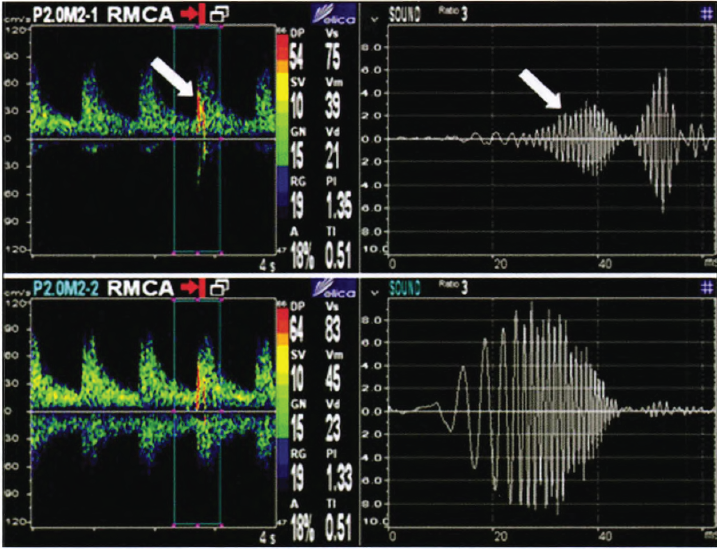

經(jīng)顱多普勒監(jiān)測MES聲譜圖